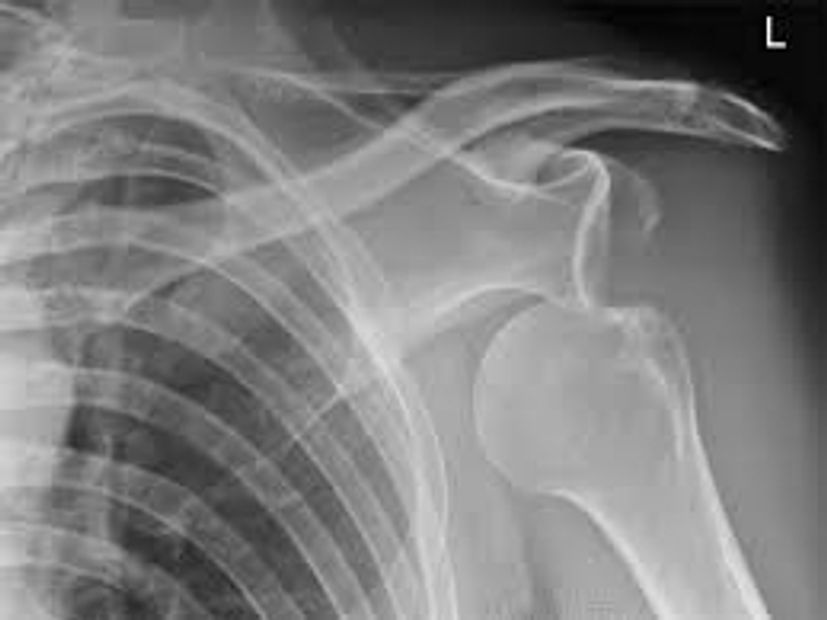

A dislocation of the joint occurs when there is a abnormal separation in the joint between two bones. The dislocation often occurs in a child or infant in a sudden impact of the joint or a fall.

Further complications and damage to nerves, ligaments,tendons and muscles. One common form of dislocation is a child is the shoulder joints due to swing the child/infant by the arms causing jerking of the joint.